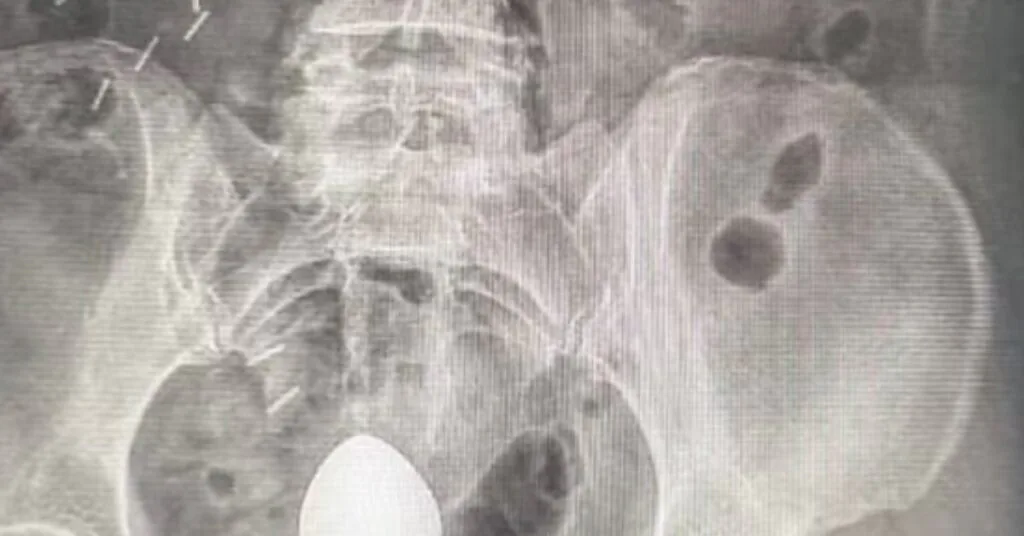

El caso de una paciente que necesitó atención médica de emergencia después de que un plug anal quedara atrapado en su intestino sirve como una alerta importante sobre el uso inadecuado de accesorios y el peligro de intentar resolver problemas de salud de forma improvisada.

A diferencia de lo que se pueda imaginar, la paciente relató que la introducción del objeto no tuvo finalidad sexual, sino la intención de aliviar el estreñimiento intestinal.

Alrededor de las 7:00 h, se introdujo el accesorio; cerca de dos horas después, al sentarse, se dio cuenta de que el objeto había sido “succionado” hacia una región donde ya no era posible la extracción manual.

¿Por qué el objeto “sube”? El intestino realiza movimientos involuntarios llamados peristaltismo, que sirven para empujar el contenido intestinal. Sumado al vacío natural del recto, cualquier objeto sin una base de seguridad adecuada puede ser llevado hacia partes más profundas del colon.

En el caso específico de esta paciente, el riesgo era aún mayor debido a la presencia de pólipos (crecimientos en la mucosa que pueden evolucionar a cáncer), lo que hace que la pared intestinal sea más sensible y susceptible a perforaciones.